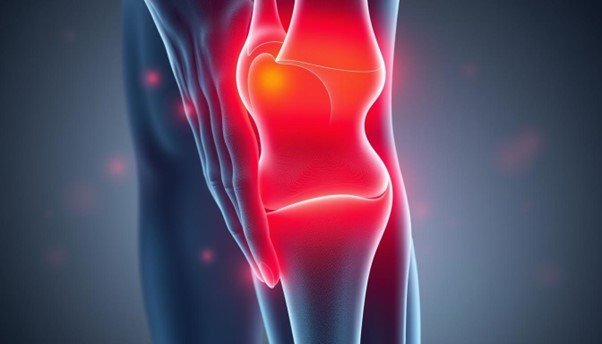

Nyeri sendi adalah masalah umum yang banyak orang alami. Ini bisa mengganggu aktivitas sehari-hari dan kualitas hidup. Kami akan jelaskan lebih lanjut tentang definisi nyeri sendi dan penyebabnya.

Nyeri sendi adalah ketidaknyamanan di area sendi. Ini bisa berlangsung dari waktu ke waktu. Penyebab umum termasuk arthritis, yang menyebabkan peradangan dan kerusakan pada jaringan sendi.

Rasa sakit ini bisa sangat mempengaruhi mobilitas kita.

Ada banyak penyebab nyeri sendi yang perlu kita pahami. Beberapa penyebab utama antara lain:

- Arthritis, yang menyebabkan peradangan dan kerusakan pada sendi.

- Cedera akibat aktivitas fisik intens atau kecelakaan.

- Infeksi yang menyebabkan peradangan pada sendi.

- Kondisi kronis seperti lupus yang memengaruhi jaringan tubuh, termasuk sendi.

Faktor risiko lainnya termasuk usia yang semakin tua, obesitas, dan riwayat keluarga. Semua ini bisa meningkatkan risiko nyeri sendi.